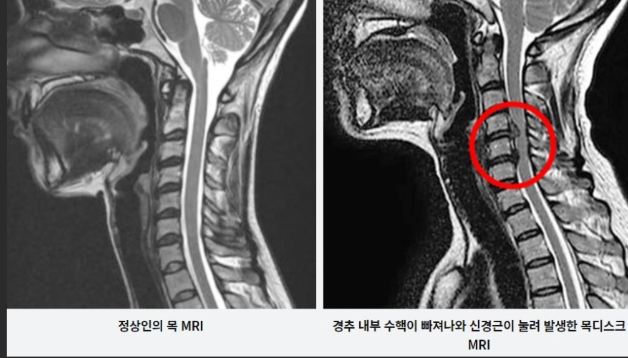

경추 추간판 탈출증은 목 부위에 있는 추간판의 내부 젤 같은 수핵이 외부 섬유 고리인 섬유테의 찢어짐을 통해 돌출될 때 발생합니다. 이 탈장은 인근 신경이나 척수에 영향을 미쳐 강도와 성격이 다양할 수 있는 다양한 증상을 유발할 수 있습니다. 이러한 증상을 이해하는 것은 조기 발견과 효과적인 관리에 매우 중요합니다.